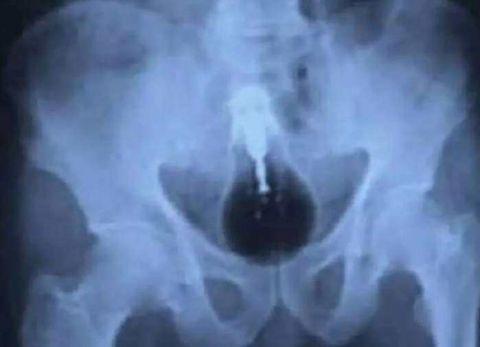

这里面装的*品毒**